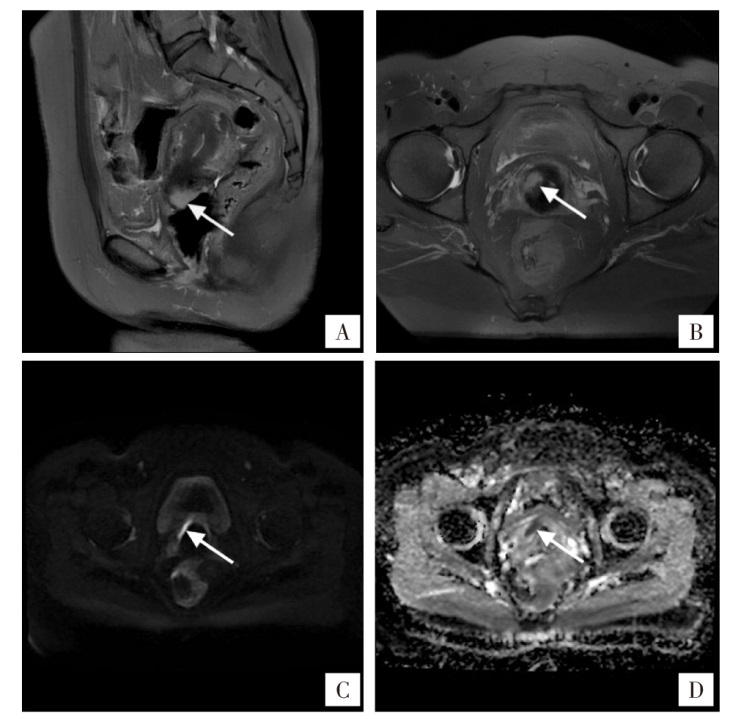

梁静, 张铭, 吴兰, 等. 子宫颈淋巴上皮瘤样癌6例临床分析[J]. 现代肿瘤医学, 2025, 33(10):1764-1770. doi: 10.3969/j.issn.1672-4992.2025.10.017.